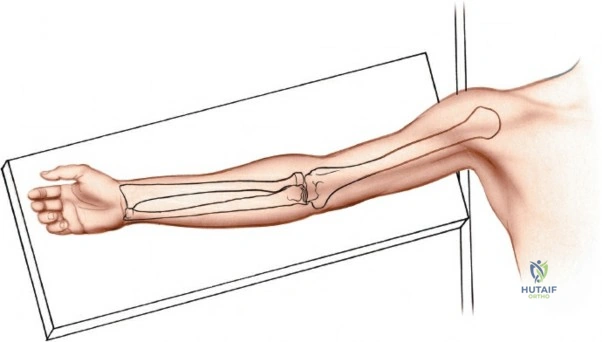

Patient Positioning and Operating Room Setup

Place the patient supine on the operating table. The affected upper extremity is extended onto a radiolucent hand table or arm board. The shoulder should be abducted to approximately 90 degrees, and the elbow extended. A pneumatic tourniquet is applied high on the brachium. The setup must allow for unimpeded use of intraoperative fluoroscopy (C-arm), which should be positioned parallel to the arm board to allow for easy anterior-posterior and lateral imaging without compromising the sterile field.

Landmarks and Incision Planning

Accurate identification of surface landmarks is the first step in a successful Henry approach. Palpate the biceps tendon, a stout, taut structure crossing the anterior elbow joint just medial to the brachioradialis muscle. Next, palpate the brachioradialis itself, the fleshy muscle forming the lateral border of the cubital fossa. Finally, identify the styloid process of the radius distally. Note that when the forearm is fully supinated (the anatomic position), the radial styloid is truly lateral.

Make a straight or gently curved incision beginning at the anterior flexor crease of the elbow, just lateral to the biceps tendon. Extend this incision distally toward the styloid process of the radius. The exact length and placement of the incision are dictated by the specific pathology; the approach is highly modular, and often only the proximal, middle, or distal third of the incision is required.